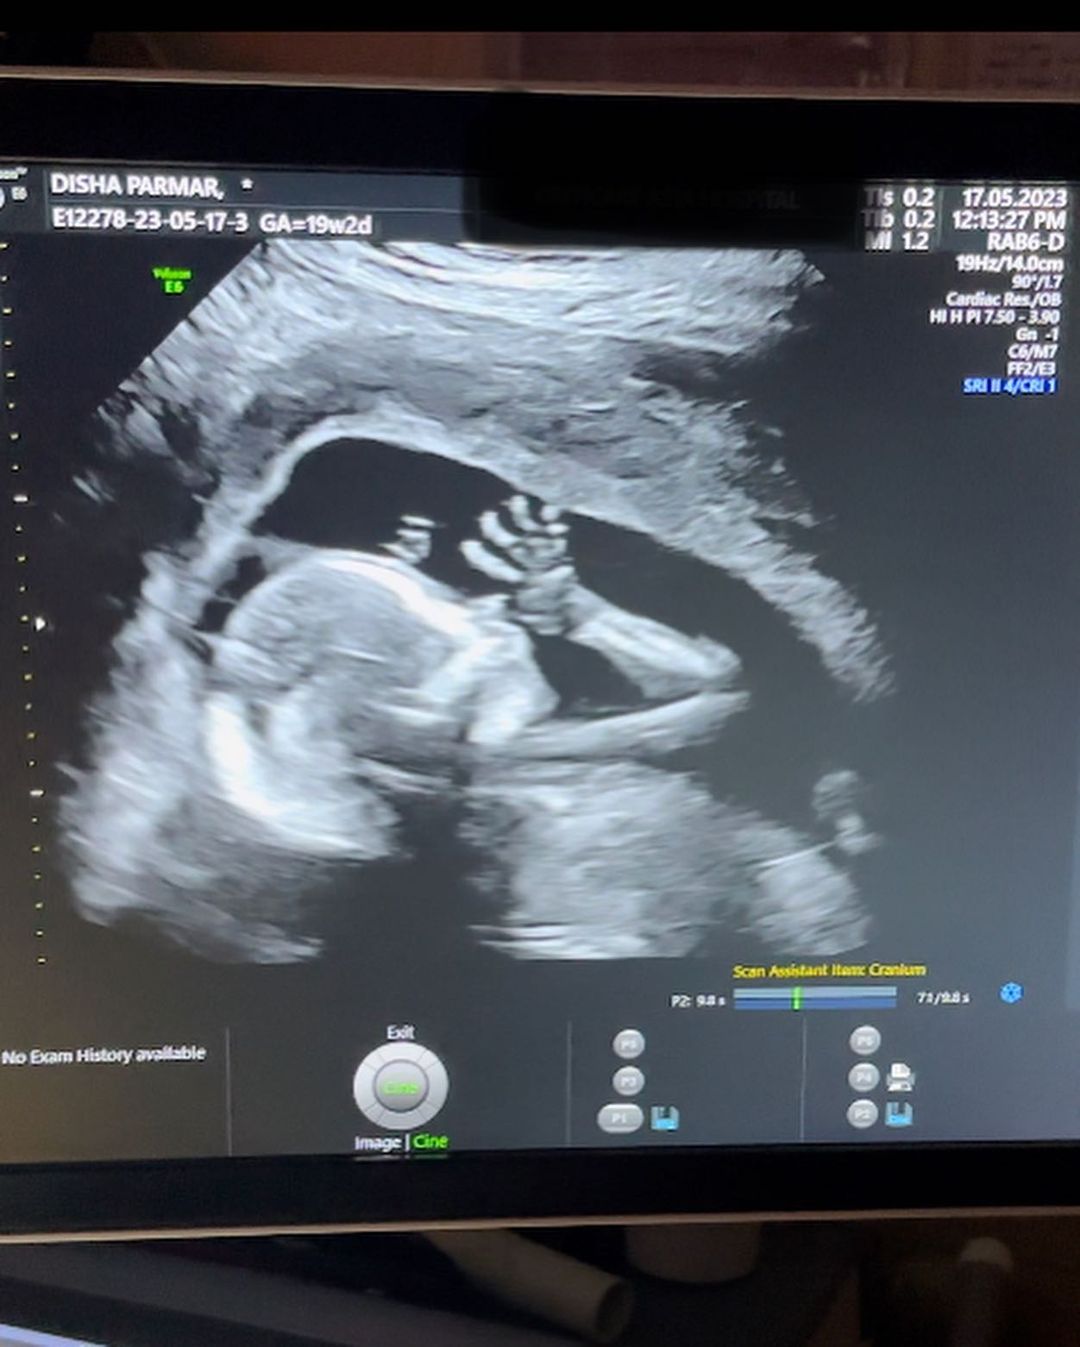

Disha and Rahul announce pregnancy : રાહુલ વૈદ્ય અને દિશા પરમાર અત્યારે ખુશીથી ફૂલ્યા નહિ સમાઇ રહ્યા હોય કારણ કે રાહુલ અને દિશા ટૂંક સમયમાં જ માતા-પિતા બનવા જઇ રહ્યા છે. આ ખુશખબર તેમણે પોતે ખૂબ જ ક્યૂટ અંદાજમાં ફેન્સ સાથે શેર કરી છે. દિશા પરમાર પ્રેગ્નેટ છે અને તેણે તેના ચાહકો સાથે આ ખુશી શેર કરવા માટે એક અનોખી રીત પસંદ કરી છે. દિશાએ કેટલીક તસવીરો સાથે સોનોગ્રાફીનો એક વીડિયો પણ શેર કર્યો છે.

જેમાં બાળક સ્પષ્ટ દેખાઈ રહ્યું છે. દિશા પરમારે ઈન્સ્ટાગ્રામ એકાઉન્ટ પર એક પોસ્ટ કરી છે. આ તસવીરમાં રાહુલ પરમાર હાથમાં સ્લેટ પકડે છે અને દિશા પરમારે તેના ખભા પર હાથ મૂક્યો છે. સ્લેટ પર લખ્યું છે, ‘મમ્મી અને ડેડી.’ આ તસવીરમાં દિશા પરમારનો બેબી બમ્પ પણ દેખાઈ રહ્યો છે. સોનોગ્રાફીના વીડિયોમાં બાળક હલતું જોવા મળે છે. આ પોસ્ટ સાથે દિશા પરમારે લખ્યું છે કે, ‘પેરેન્ટ્સ અને બેબી તરફથી હેલો.’